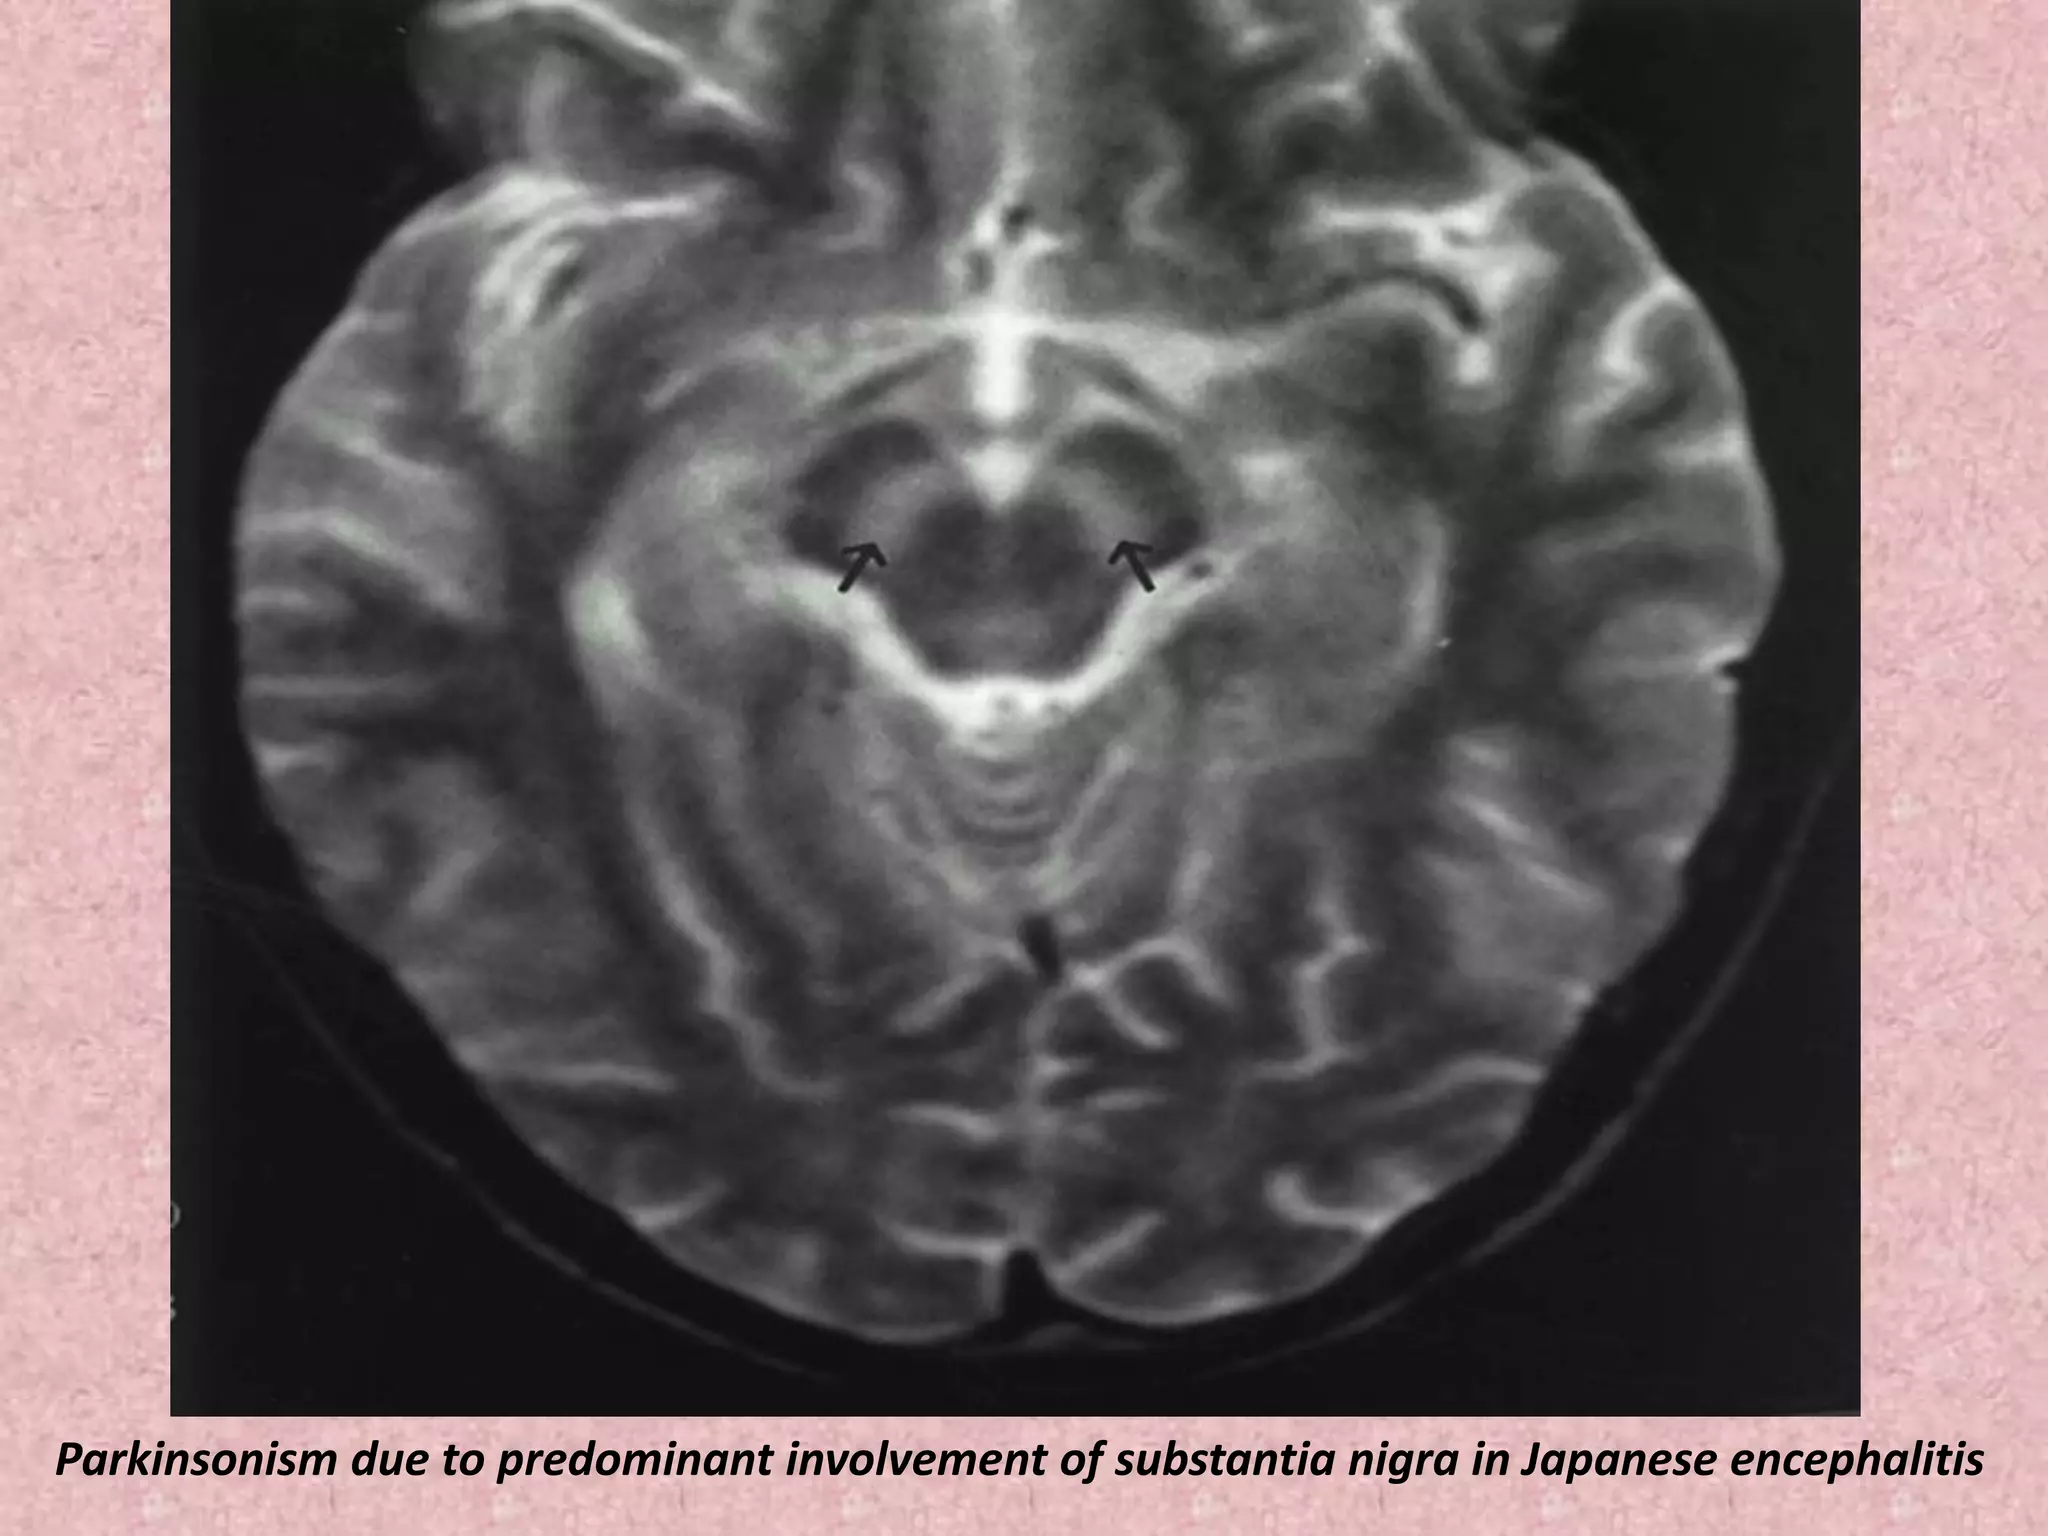

Parkinsonism due to predominant involvement of substantia nigra in Japanese encephalitis

Parkinsonism due topredominant involvement of substantia nigra in Japanese encephalitis